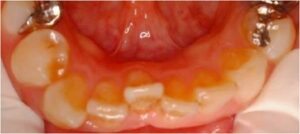

歯に詰めるプラスチックが危ない パート2

1月15日に、奥歯に詰めたプラスチックの周りから虫歯になっている人が非常に多いという話をしました。 今日もそんな患者様がいらっしゃいました。下の写真です。 麻酔をして、プラスチックを外すと、前回のように虫歯が拡がってボロボロというほどではな […] 本文を読む